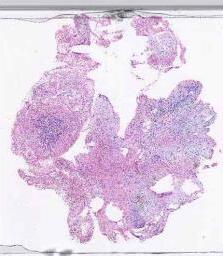

临床资料: 女,14岁,主因“发现盆腔包块13天”入院。冰冻送检:左卵巢肿物:灰白灰红碎组织一堆,大小27cm×19.5cm×6.5cm,切面灰白灰黄灰红,实性质软。既往“社区获得性肺炎、急性上呼吸道感染”于外院住院治疗,现恢复可,3天前复查血常规未见明显异常。否认传染病或慢性病史,否认药物或食物过敏史,否认其它手术史及外伤史,否认输血及输血制品史,预防接种史不详。盆腔可扪及一巨大肿物,大小约20×18cm,囊实性,轮廓清,活动受限,无压痛。2025-05-17外院肿瘤标志物:CA125115U/mL,余未见明显异常2025-05-22我院甲胎蛋白10.7ng/m,CA125133.0U/mL,CA153、CA199等肿瘤标志物未见异常。2025-05-21我院彩超:盆腔内可见大小约170×141×116mm的的肿块图像,形状呈椭圆形,内部为类实质样低回声,分布不均质,其内可见散在无回声区及多条短线状强回声,边界清楚,性质待定,考虑畸胎瘤可能,囊腺瘤不除外;盆腔内可见深约25mm液性暗区,考虑盆腔积液。